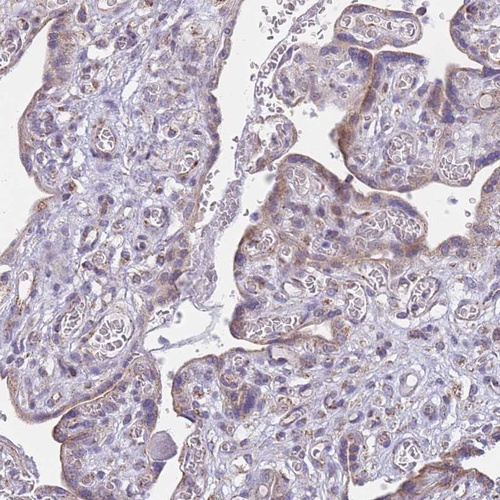

Immunohistochemical staining of human testis shows moderate to strong granular cytoplasmic positivity in Leydig cells.